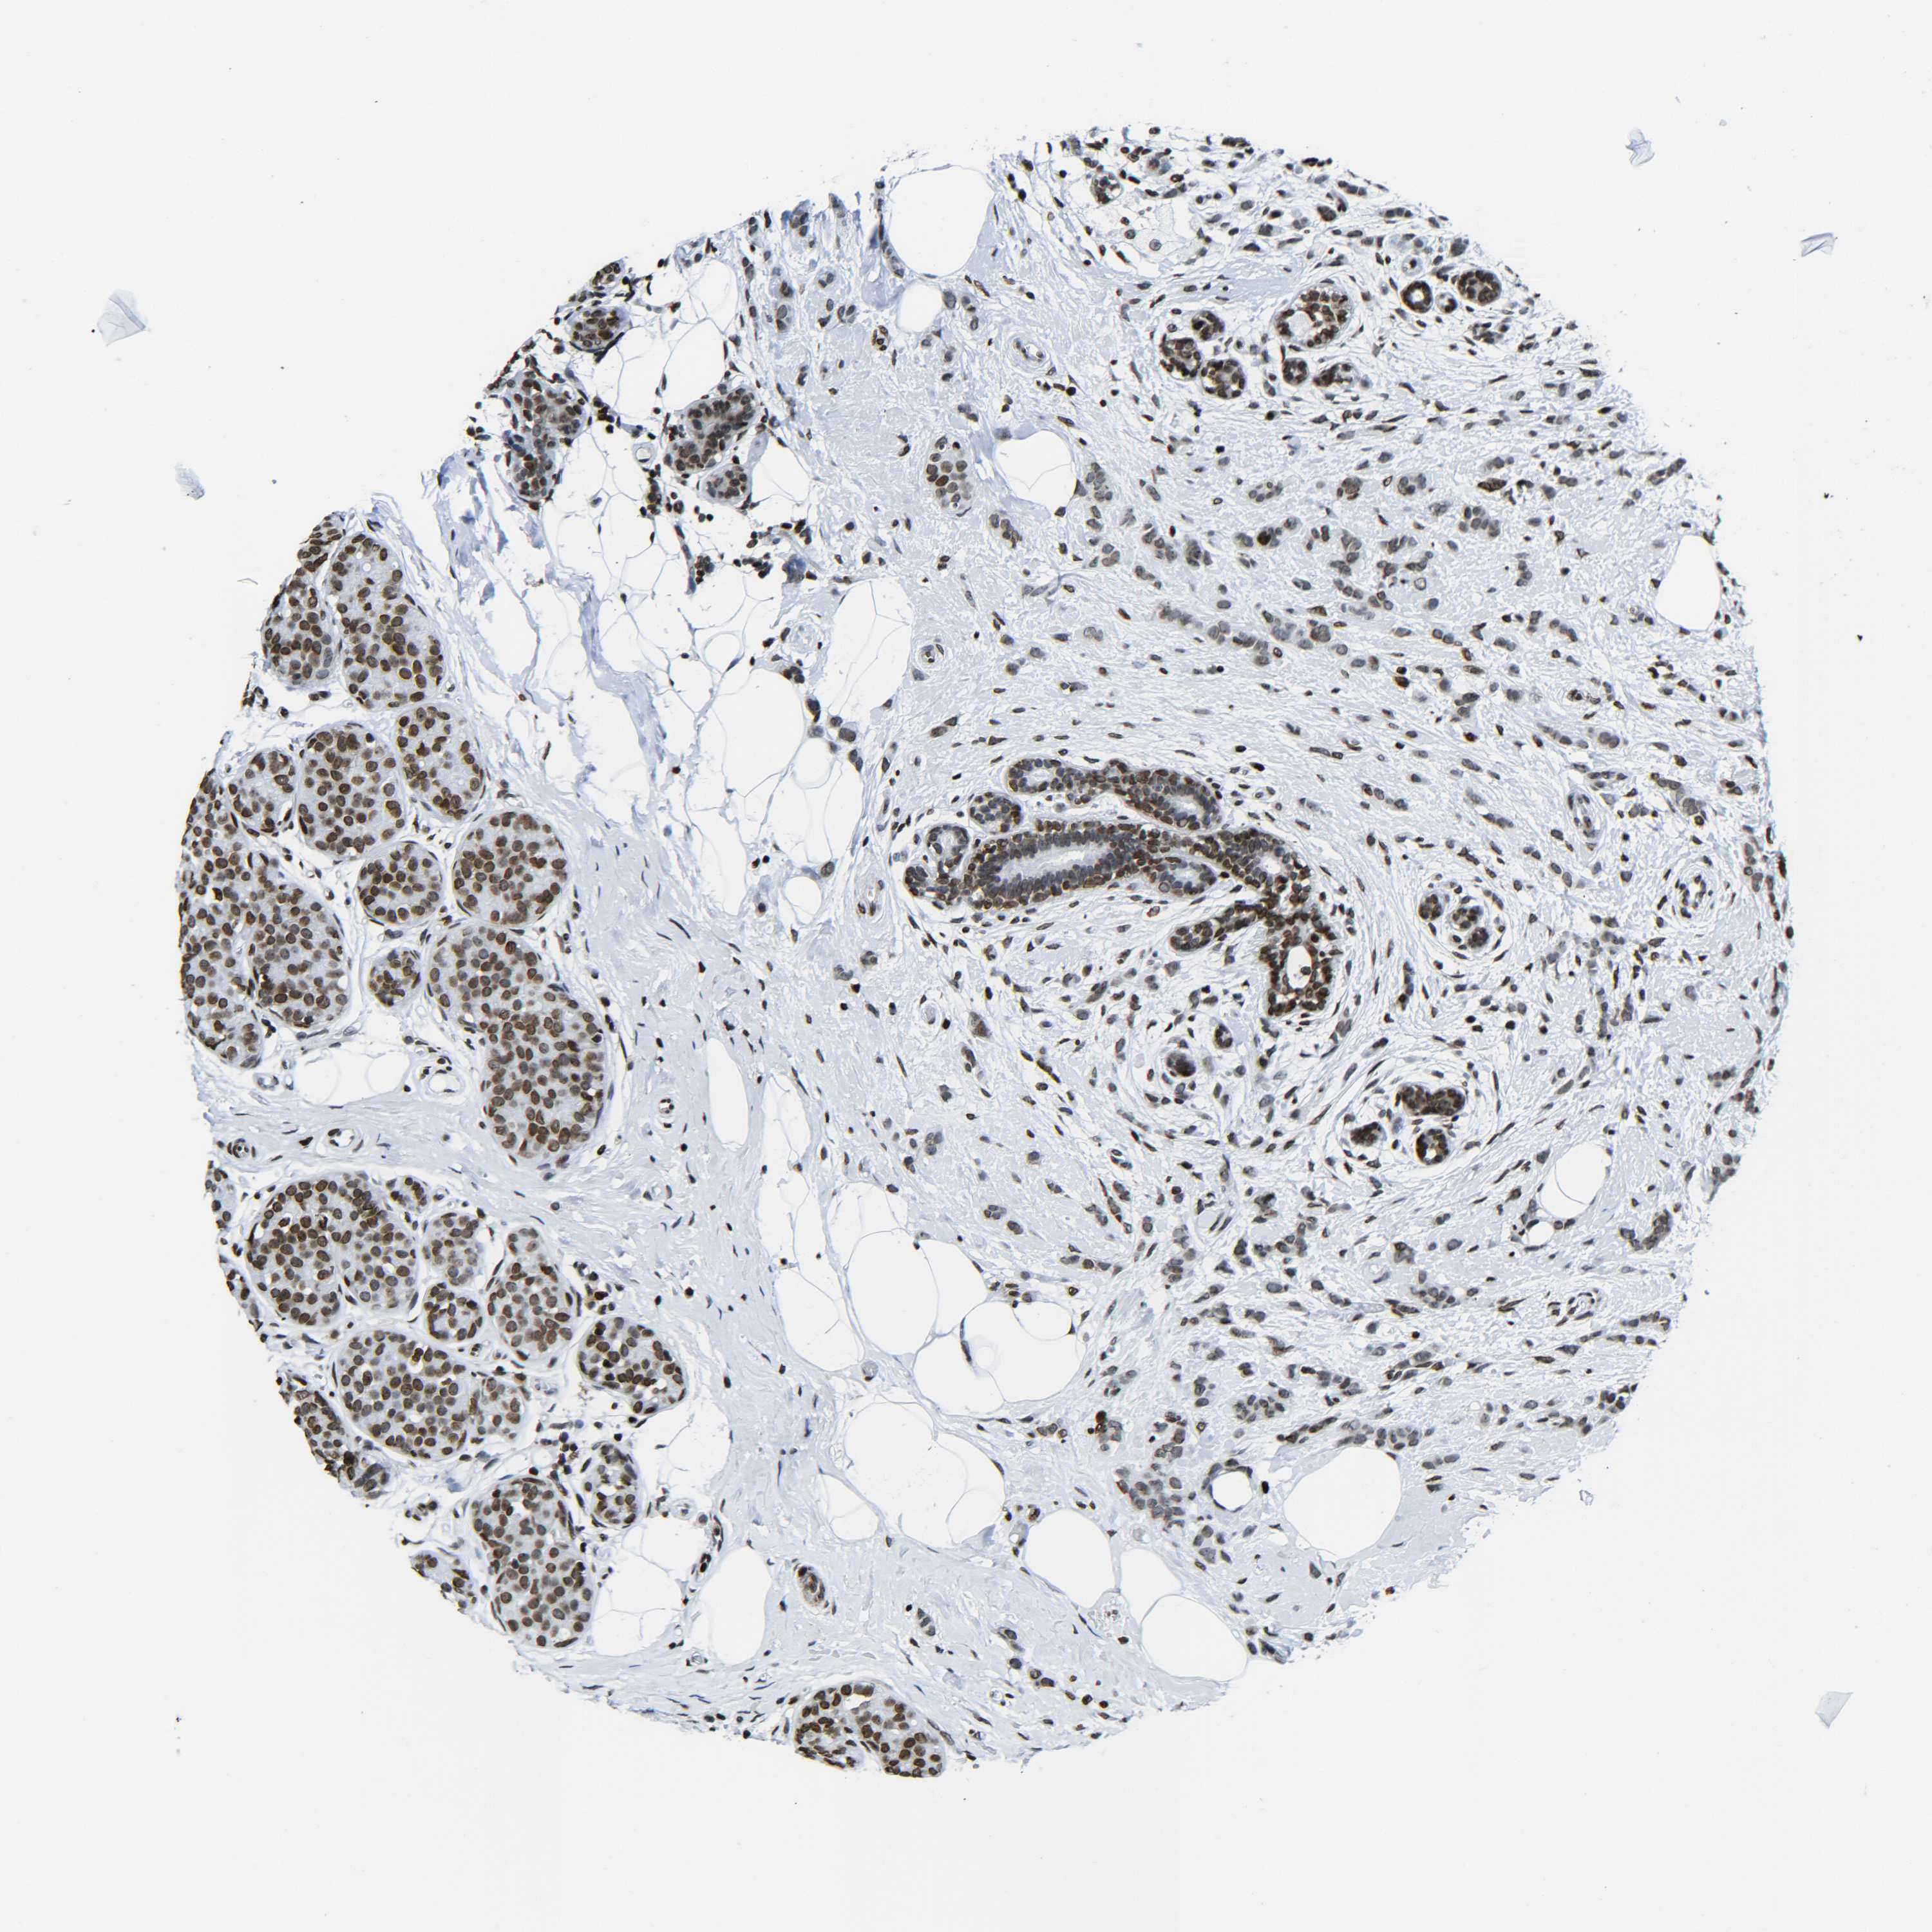

H2AX

• H2AX